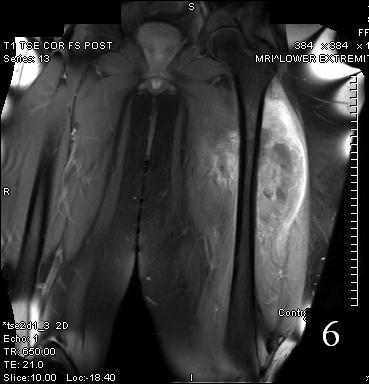

GENERAL INFORMATION Tumoral calcinosis is a very rare entity, characterized by large tumorlike calcium deposits and painless mass, arising near to the articular soft tissue areas. Common areas affected are elbows, hips, knees rarely involve hands and feet. No obvious...